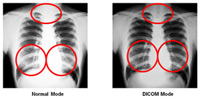

DICOM Simulation Mode

DICOM

(

Digital Imaging and Communication in Medicine) is a standard for

handling, storing, printing, and transmitting information in medical

imaging, which includes a file format definition and a network

communications protocol. The DICOM simulation mode in the EB-1965 can

reproduce images with gray level very close to DICOM Part 14 (Grayscale

Standard Display Function). This mode is ideal for viewing grayscale

medical images such as X-ray pictures for training and education in the

medical institutions.